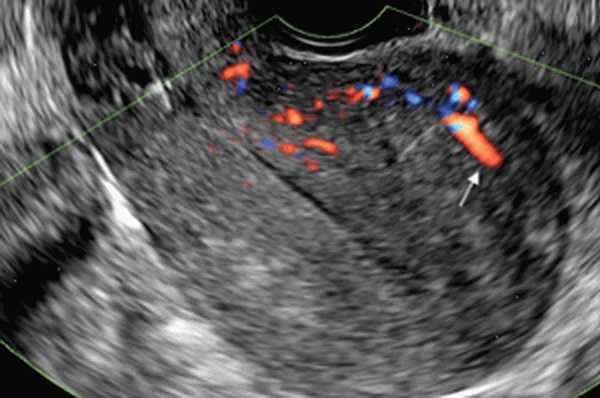

УЗИ при аденомиозе

УЗ-сканирование трансвагинальным датчиком [11] [12] [13] дает наиболее информативные данные о патологии. Для более точной диагностики исследование также стоит проводить незадолго до начала менструации. Однако достоверность ультразвукового исследования значительно снижается при диффузной форме аденомиоза.

Основным методом диагностики является УЗИ. Наиболее точные результаты (около 90%) обеспечиваются при проведении трансвагинального ультразвукового сканирования, которое, как и гинекологический осмотр, выполняется накануне менструации. Об аденомиозе свидетельствует увеличение и шаровидная форма органа, различная толщина стенок и кистозные образования размером более 3 мм, появляющиеся в стенке матки незадолго до менструации. При диффузном аденомиозе эффективность УЗИ снижается. Наиболее эффективным диагностическим методом при этой форме заболевания является гистероскопия.

Для подтверждения диагноза проводят ультразвуковое исследование. УЗИ - наиболее точный метод диагностики аденомиоза. Исследование проводят трансвагинальным способом, т. е. через влагалище. Процедуру тоже назначают накануне менструаций. Признаки аденомиоза матки на УЗИ:

- шаровидная увеличенная форма матки;

- разная толщина стенок органа;

- кистозные образования размером более 3 мм (можно обнаружить незадолго до менструации).

К эхографическим признакам аденомиоза также относят изменение плотности тканей матки. Еще на заболевание указывают участки с гипоэхогенностью (темные пятна), гиперэхогенностью (светло-серые пятна) и гетероэхогенностью (темные и светлые вкрапления в одном месте).